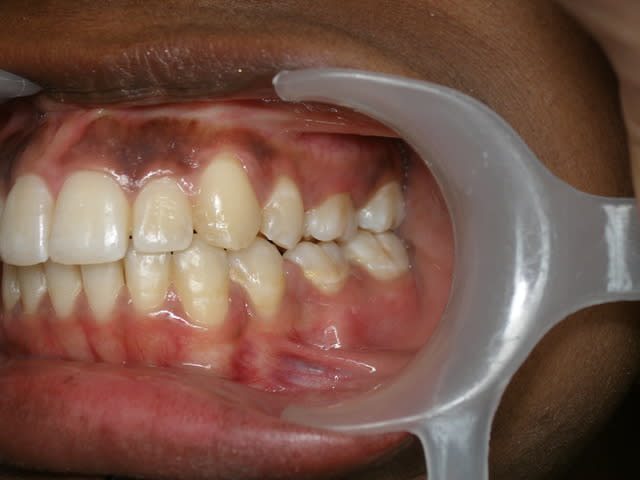

Dans ces deux cas-ci dont je joins les photos, je ne vois pas très bien comment tu aurais pu faire avec ta méthode. Le premier avait 4 canines incluses, j’ai utilisé un système traditionnel en haut (boutons collés sur les couronnes, ligatures et traction par cantilever) et des ligatures collées directement sur les couronnes et traction par CT8-1 en bas. Pour le second, je me suis servi de l’alvéole déshabitée de la 53 pour passer la ligature, avec un CT8-1. Dans ce dernier cas, où aurais-tu mis ta vis ?

Daniel